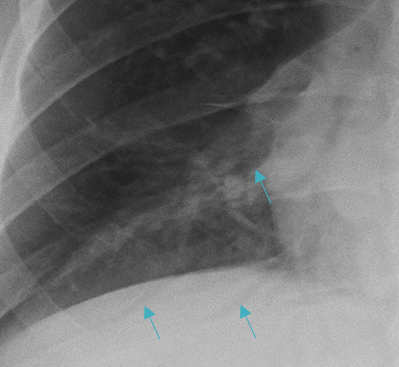

Deep Sulcus Sign

In patients who are upright when imaged, such as for a PA/lateral CXR, air in the pleural space from a pneumothorax tends to collect in non-dependent locations, such as the apices.

Left Apical Pneumothorax

In patients who are supine, air may collect at the bases and anterior chest, potentially resulting in a deep sulcus sign, which indicates a pneumothorax.

Deep Sulcus on Right (Yellow Arrows) on Supine Radiograph